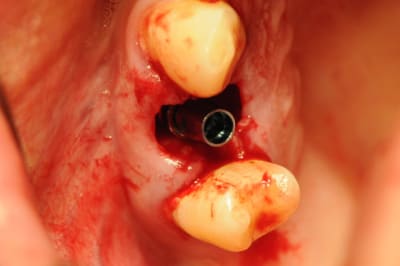

Le second cas :

Je l'ais fait ce matin même justement (ce soir, je ne parviens pas à trouver le sommeil).

comme vous pouvez le constater, l'os en palatin à complètement foutu le camp. J'ai donc mis une membrane et un peu de substitut osseux.

Nous voilà donc à la mise en vitrine immédiate.

Je prend un peu de composite flow pour respecter au mieux l'architecture exacte de la gencive.

J'essaie de maintenir le composite à au moins 1 mm du col de l'implant.

bien que ce ne soit pas absolument nécessaire, je met un fil de suture pour rendre un peu plus hermétique la fermeture autour de la dent provisoire.

puis je monte progressivement mon composite.

Je suis encore un peu timide avec la mise en charge immédiate.

pour moi, le maintien de papilles est le plus important, je n'ose pas mettre " en charge" la dent même avec une très faible sous occlusion.